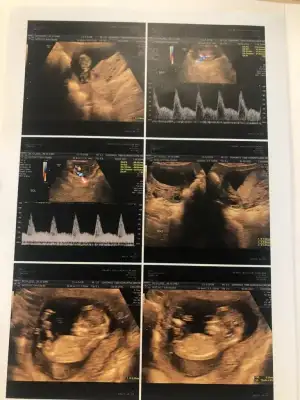

dr soylemeden siz gorun genital nub teorisi ( bebegin cinsiyeti)

dün 2 li tarama testine girdim bebeğim uyuyordu doktor cinsiyet tahmini yapmadı renkli ultrasonografi görüntülerim var, bu resimlere göre cinsiyet tahmini yapabilirmsiiniz , bu ikinci gebeliğim 8,5 yaşında bir kızım var